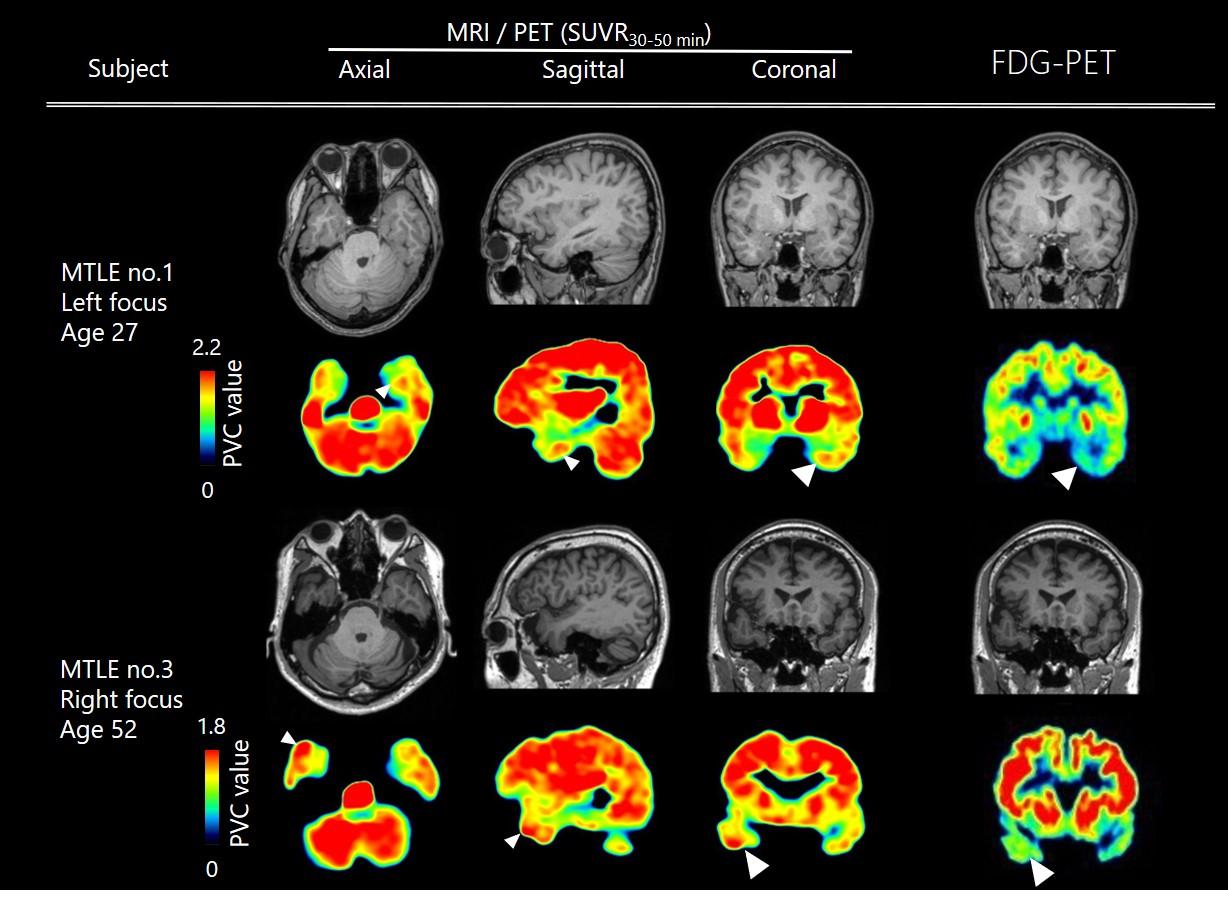

A research group led by Professor Takuya Takahashi and Associate Professor Tomoyuki Miyazaki of the Department of Physiology, Yokohama City University Graduate School of Medicine, in collaboration with the National Institutes for Quantum and Radiological Science and Technology and Keio University, has succeeded for the first time in the world in developing a tracer (compound) for positron emission tomography (PET) that visualizes AMPA receptors—the most critical molecules for brain function—in the living human brain. Using this tracer, they successfully observed a high accumulation of AMPA receptors in the focal region of medial temporal lobe epilepsy (see figure). AMPA receptors are the most important molecules supporting brain function. Visualizing these molecules in the living human brain is expected to dramatically advance the elucidation of the pathophysiology of psychiatric and neurological disorders, which has been a black box until now, and lead to the development of innovative diagnostic and therapeutic methods based on this information. Currently, using this PET tracer, a multi-center, investigator-initiated clinical trial is underway at eight institutions nationwide, with Yokohama City University Hospital as the lead institution, aiming for regulatory approval of a diagnostic agent for epilepsy. It is also being used in a clinical trial for post-stroke patients of Edonerpic Maleate (Abe et al., *Science* 2018), a drug identified by the same group in 2018 to promote the effects of post-stroke rehabilitation, to verify its effectiveness as a biomarker for functional recovery. The group is also conducting imaging of patients with psychiatric disorders in collaboration with the Department of Psychiatry at Keio University, the University of Fukui, Kyushu University, and others.

Figure: Image of a patient with medial temporal lobe epilepsy using an AMPA receptor PET probe. The arrow indicates the clinically identified epileptic focus. An increase in AMPA receptors is observed.